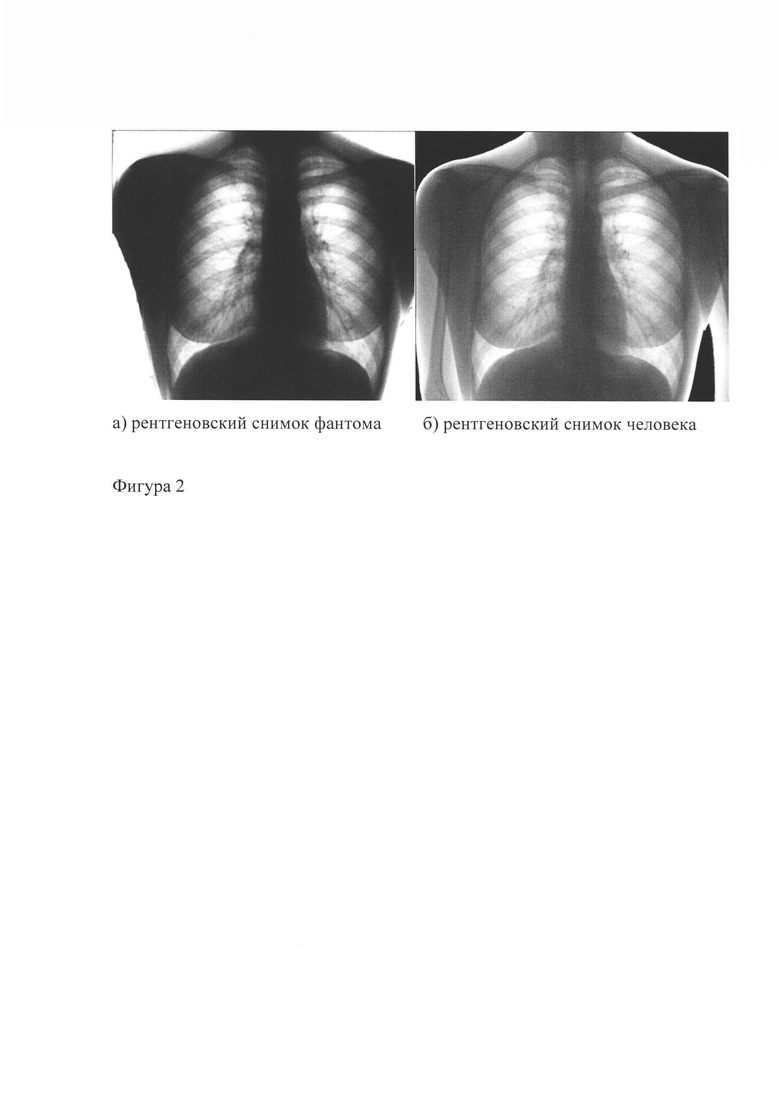

На фигуре 2 представлены рентгеновские снимки фантома без использования имитаторов патологий и человека, рентгенограмма которого используется как прототип, где а) - рентгеновский снимок фантома, б) - рентгеновский снимок человека.

В процессе использования фантом фиксируют в камере рентгеновского или флюорографического аппарата. При необходимости к корпусу фантома прикрепляют имитаторы патологий в местах, где должна наблюдаться та или иная патология. При производстве снимка на экране виден рентгеновский снимок фантома без патологий, фиг. 2, или, если прикреплены имитаторы патологий, то виден рентгеновский снимок фантома с патологиями, фиг. 3.